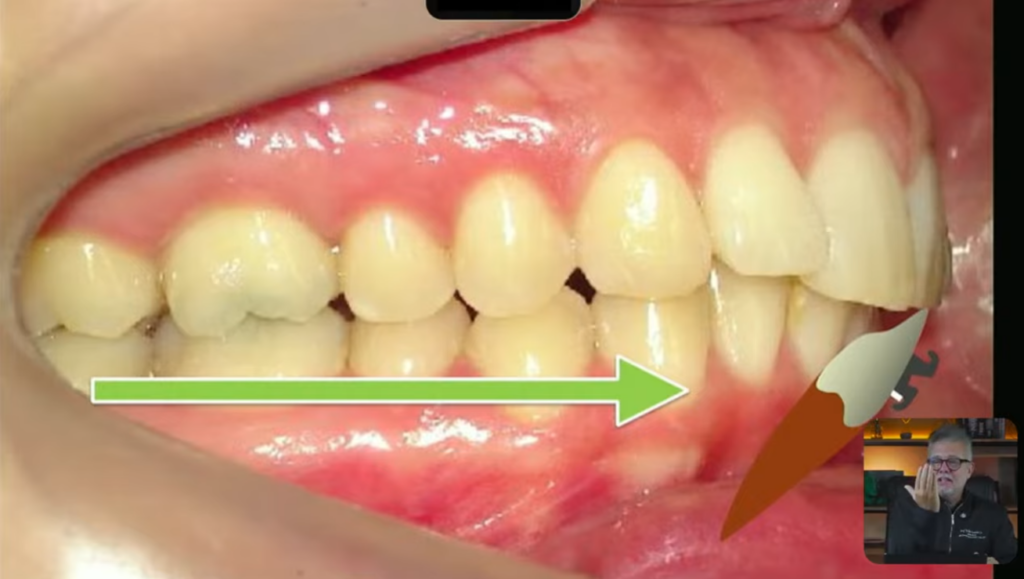

Eu vou pegar essa boca, que vocês estão percebendo que nós temos uma classe 2, e nós vamos tratar essa boquinha aqui com elástico:

E essa imagem dessa classe 2, quando eu utilizo um elástico de classe 2, os dentes inferiores, eles vestibularizam, o inferior sempre mesializa mais do que o superior distaliza,

pode acontecer uma lingualização dos incisivos superiores, isso é uma das coisas que acontece:

O efeito colateral que acontece nos incisivos inferiores, quando a gente utiliza o elástico de classe 2, é um efeito de vestibularização no incisivo inferior:

Então a gente vê demais o paciente inclinando o incisivo para vestibular, como que eu faço para não inclinar esse incisivo para vestibular pessoal?

Eu vou utilizar um torque resistente lingual nesse incisivo, que pode ser um torque resistente lingual feito pelo próprio bracket